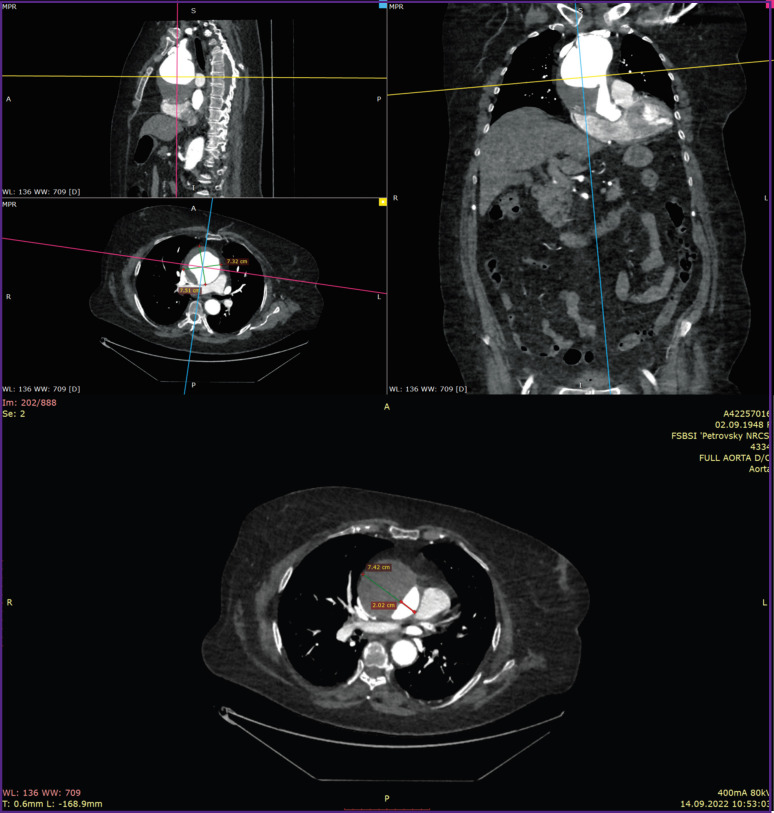

Materials and methods: The study experimental material was the resected parts of the aortic aneurysm obtained during aneurysm replacement surgery in a patient with uncontrolled arterial hypertension. The direct mechanical testing methods such as instrumental indentation and uniaxial extension were used.

Results: It was shown that by the direct instrumental indentation it is possible to accurately assess and compare the stiffness of all three layers of the aortic wall. In this clinical case, the inner aorta layer was subject to the greatest atherosclerotic damage. In the media area, the values of this indicator were widely scattered, whereas the material was greatly dissected. By uniaxial extension method it is possible to obtain accurate parameters of the vascular wall strength, as well as to assess the stiffness, elasticity, and deformability of the intraoperatively resected aortic tissue. It was found that the aneurysm aortic wall, compared with the non-dilated aortic section, was characterized by a significantly lower strength in both longitudinal (by 4.25 times) and transverse (by 3.75 times) directions. In addition, aneurysm tissues demonstrated a significantly lower elasticity and deformability.